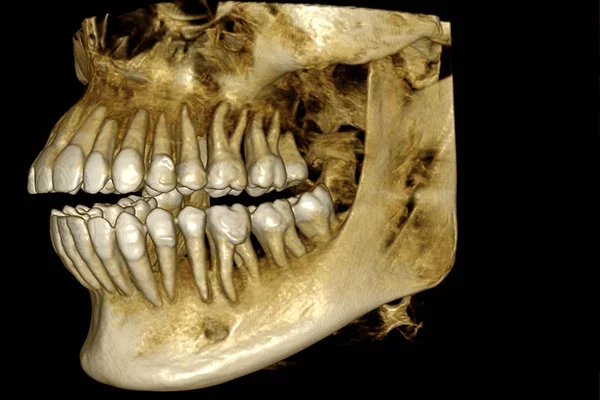

• 3D HD obraz s vysokým rozlišením 75 µm i pro velké objemy

• CAD/CAM kompatibilní-skenování otisků a odlitků a převod do stl

• Propojení s optickými stl skeny IO skenerů